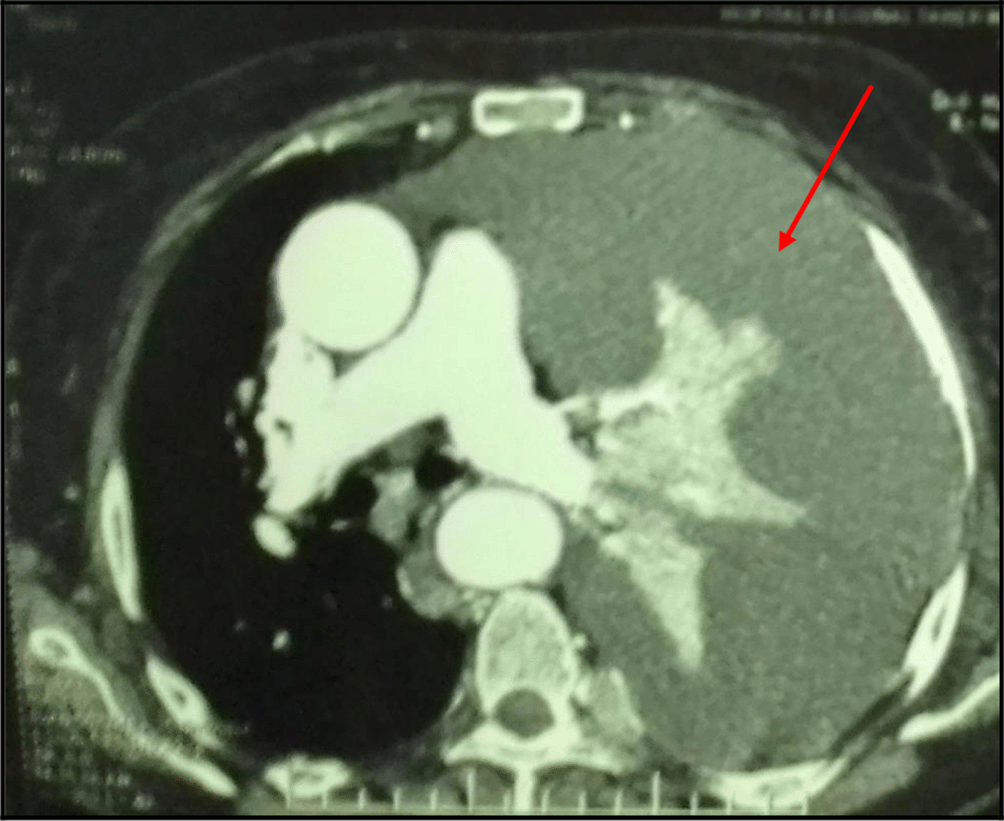

The chest X-ray showed left pleural opacity with signs of compression (Figure 1). So, an exploratory and evacuating ultrasound-guided pleural puncture was immediately performed. The thoracic ultrasound showed a massive anechoic, free left pleural effusion associated with pleural nodules (Figure 2). Analysis of the pleural fluid showed a serohaematic exudative fluid with a predominantly lymphocyte formula (80%). A Gram stain fast bacilli (AFB) stain and bacterial and tuberculosis cultures for were all negative. Therefore, a malignant origin was suspected. The chest CT-scan revealed a left-sided malignant pleural effusion associated with mediastinal adenopathy, extended secondary bone lesions and subcutaneous lesions (Figure 3). Additionally, the echocardiography was normal.